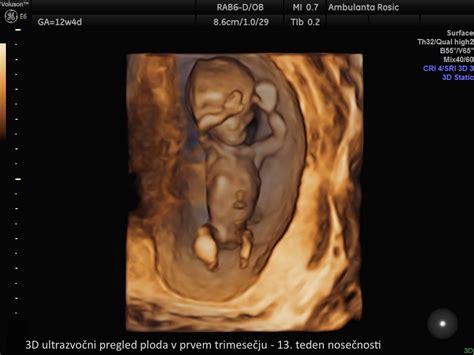

3D Ultrazvok: Ta tehnika ustvarja tridimenzionalne slike ploda, ki omogočajo podrobnejši vpogled v njegov videz in anatomijo. Pogosto se uporablja za bolj celovito oceno strukture ploda in lahko ponudi realističnejšo vizualizacijo obraza in telesa.

4D Ultrazvok: Nadgradnja 3D ultrazvoka, ki dodaja element gibanja v realnem času. Ustvari živo sliko ploda, kar omogoča dinamičen pogled na njegovo gibanje. 4D ultrazvok je še posebej priljubljen za zajem realističnih obraznih mimik in kretenj. Najboljši čas za 3D ali 4D ultrazvok je običajno med 24. in 28. tednom nosečnosti.